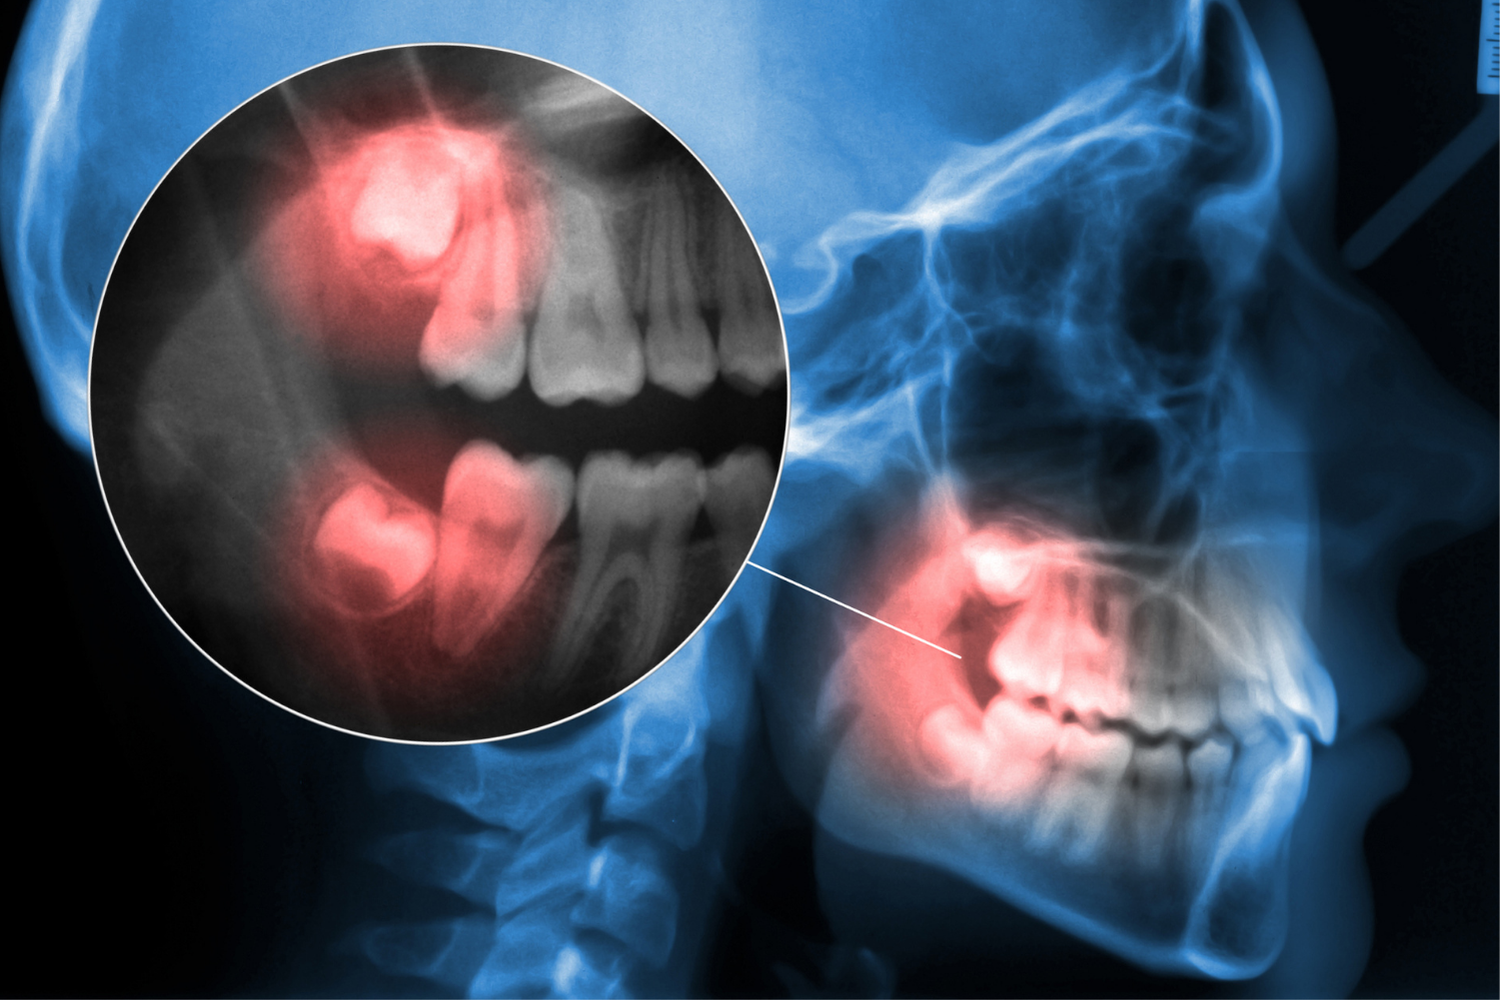

Impacted Wisdom Teeth Removal

Surgical treatment for wisdom teeth trapped beneath the gums or bone.

Wisdom teeth may need to be removed if they become impacted, cause crowding, or lead to infection and discomfort. In some cases, wisdom teeth may not have enough space to grow properly, which can lead to complications that require surgical removal.